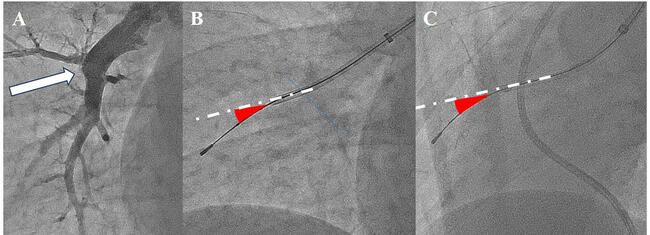

After removing ring-down artifacts, which are luminous rings of false images surrounding the IVUS catheter, the overall size of the IVUS image was adjusted to fit the screen according to the observed vessel diameter. While performing this procedure, the IVUS image was on live mode. The technique entails slightly advancing the guidewire to the organized thrombus, pushing it into the thrombus, and guiding the IVUS along the guidewire. After we confirm the position of the IVUS in the organized thrombus, the IVUS and guidewire are grasped together and advanced such that the IVUS is slightly ahead of the guidewire. Thus, instead of manipulating the guidewire through the lesion, it is crossed by pushing the IVUS forward (Figure 1, Videos 1-6). Using the ultrasound image, we confirm the presence of the IVUS in the true lumen of the vessel and continue to advance the IVUS through the lesion into the true lumen distal to the lesion. Based on their morphology, total occlusion lesions have extremely hard intimal layers,6 and advancement of the IVUS catheter alone is often prevented by the lesion. Therefore, we need to use a hard-tip guidewire from the beginning of the procedure because it is necessary to first penetrate the entrance of the obstruction with this guidewire before the IVUS can penetrate the lesion.

Target vessel angle and diameter

To determine whether the support force of the guiding catheter plays a role in the success of the precedent IVUS technique, the angle of the lesion was evaluated. Two directional views were obtained: 0º anteroposterior and 60º left anterior oblique views. We scored the angles of the lesion in these 2 views acquired at angiography to account for the effect of the degree of flexion of the target vessel, with straight lines scored as 0 points, less than 45 degrees as 1 point, between 45 and 90 degrees as 2 points, and greater than 90 degrees as 3 points. Scoring was set as the sum of the scores for the 2 angiographic views (Figure 2).